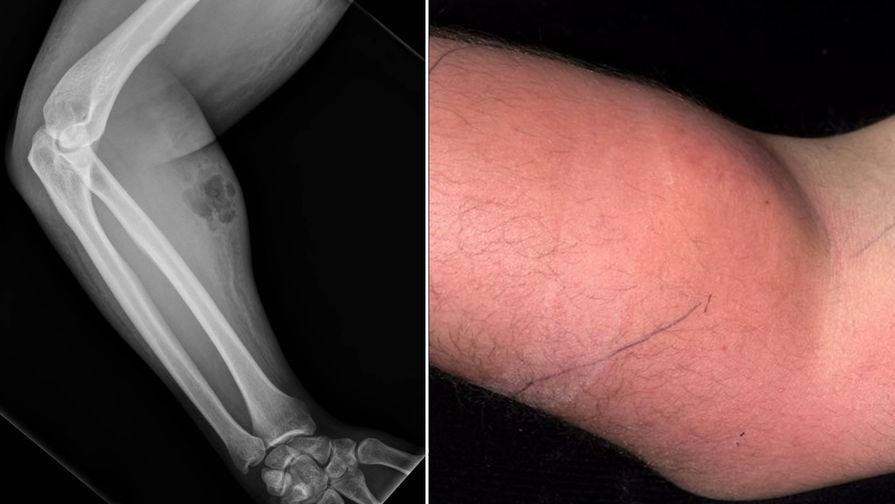

Мужчина обратился к врачам с жалобами на боль в спине. Она беспокоила его давно, но за три дня до обращения он переносил тяжелые предметы, и с тех пор боль только становилась сильнее. Осмотрев пациента, врачи обнаружили, что его правое предплечье опухло и воспалилось. Тогда то клиент и признался, что в попытках унять боль он вводил себе собственный эякулят.

Эти эксперименты привели к развитию бактериальной инфекции. Спустя 24 часа после последней инъекции она охватила все предплечье, вызвав отек и покраснение кожи.

Рентгенограмма показала подкожную эмфизему — скопление воздуха в подкожной клетчатке. Анализ крови выявил повышенное содержание С-реактивного белка, маркера воспалительных реакций, до 150 мг/л при норме до 5 мг/л, что свидетельствовало об острой инфекции. Также вдвое были повышены лейкоциты. Врачи тут же ввели мужчине антибиотики.